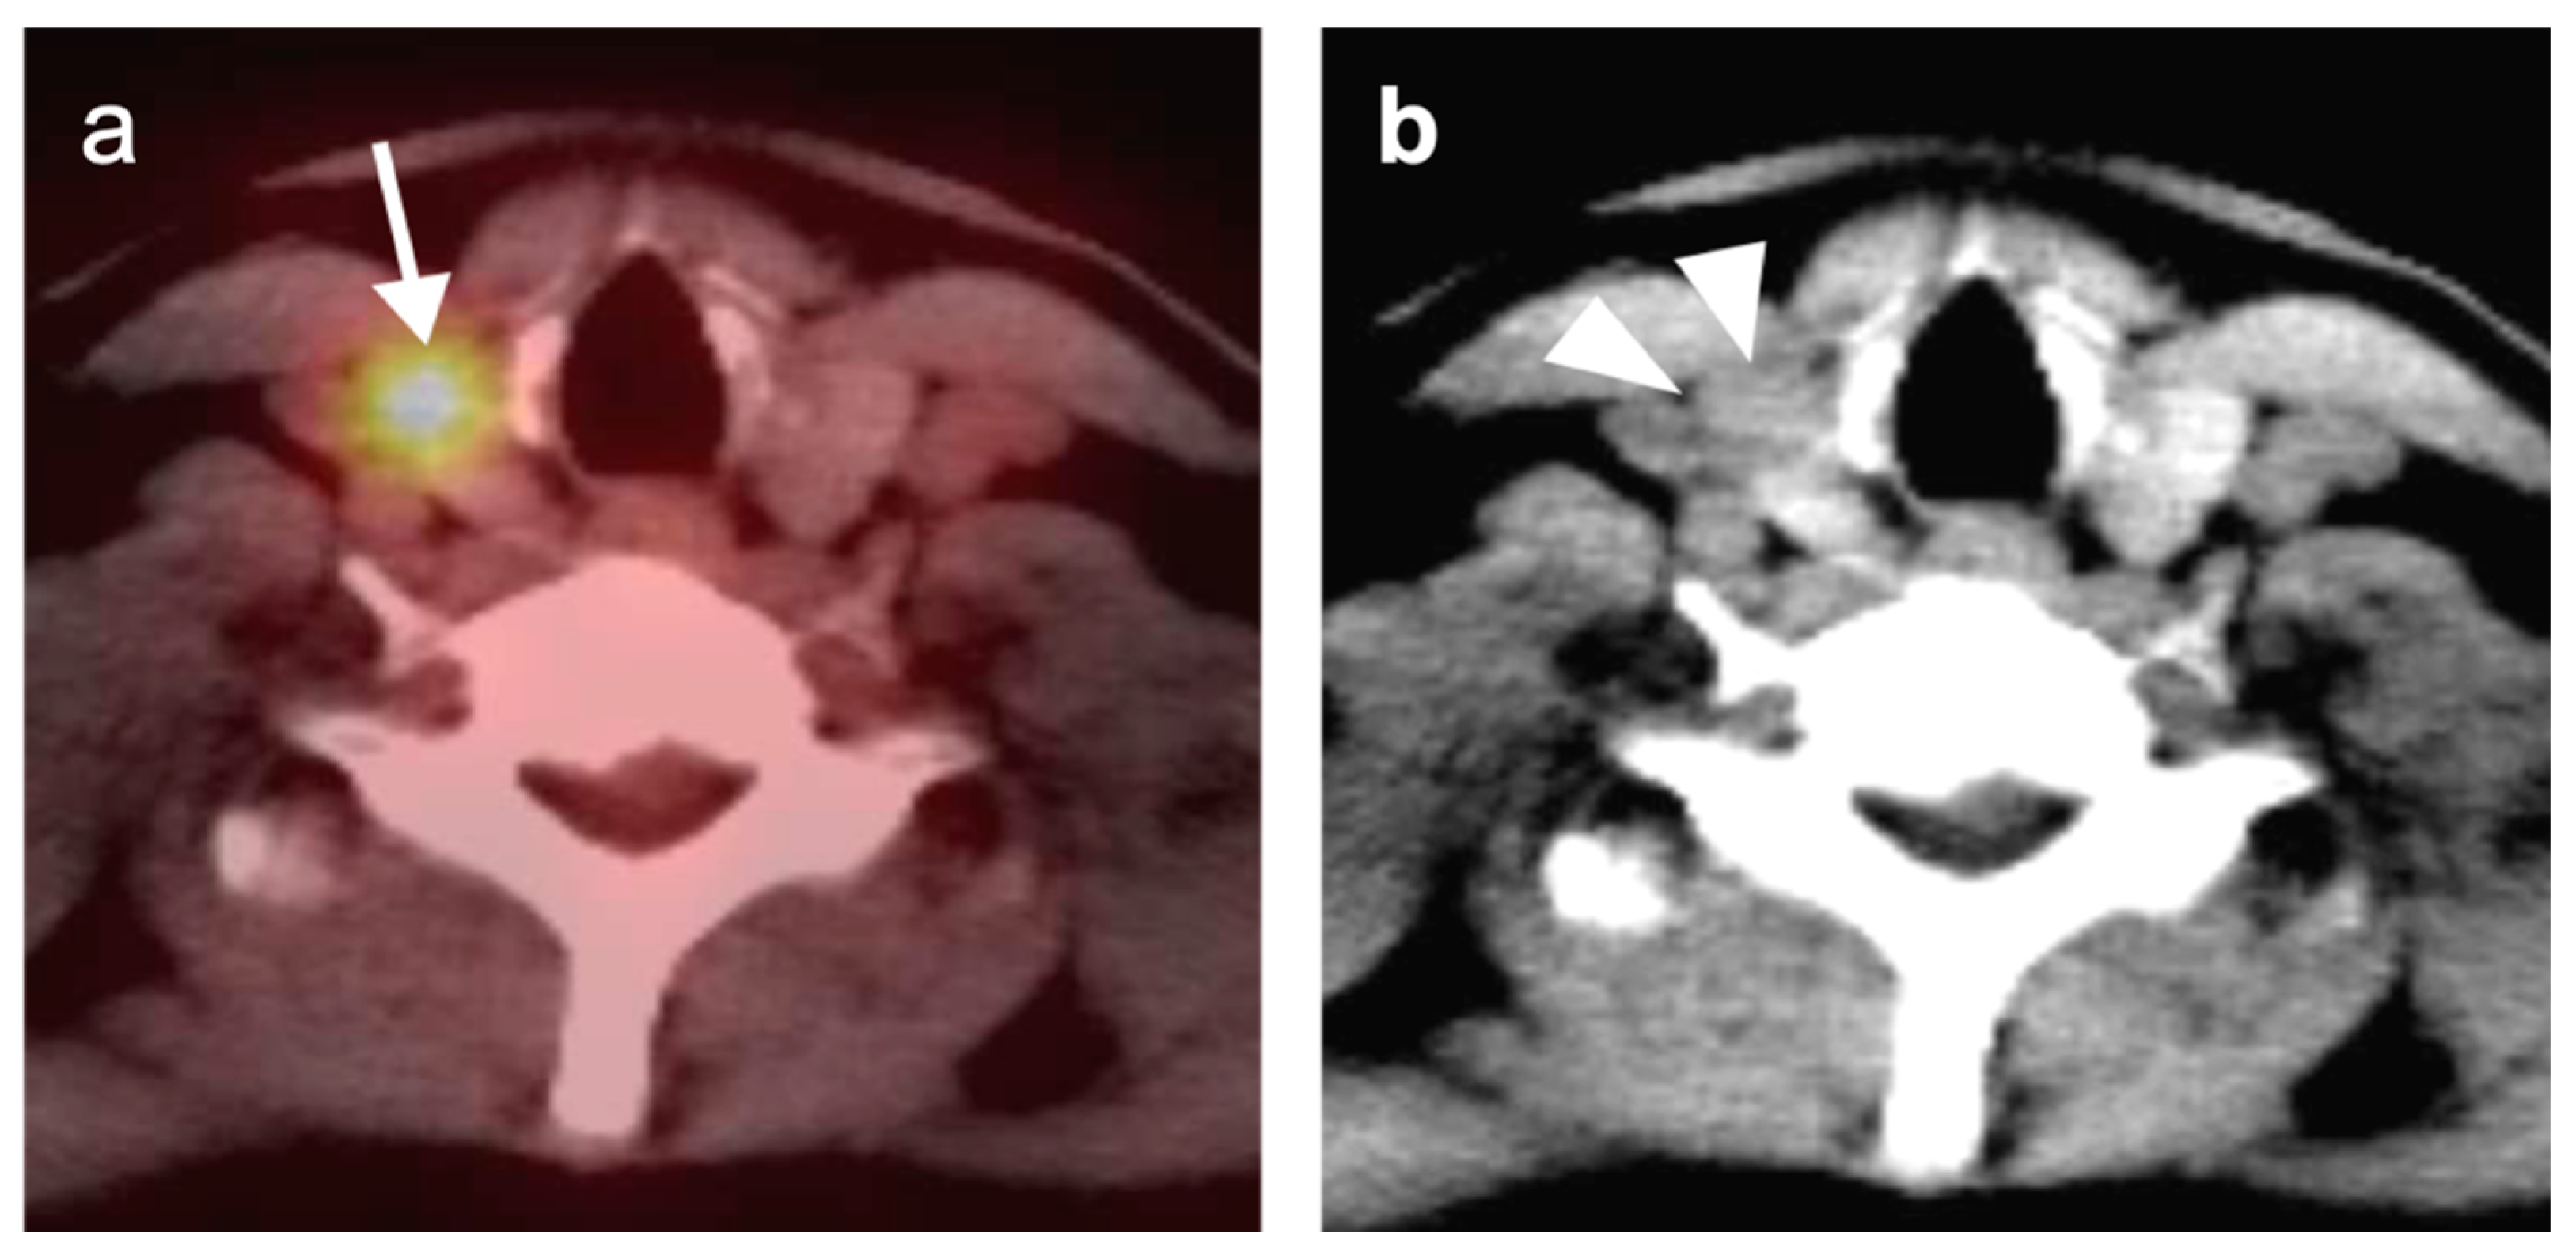

2.6. Thyroid Cancer

- Thyroid Incidentaloma

- 2.

- Differentiated thyroid cancer

- 3.

- Anaplastic thyroid cancer

- 4.

- Medullary thyroid cancer